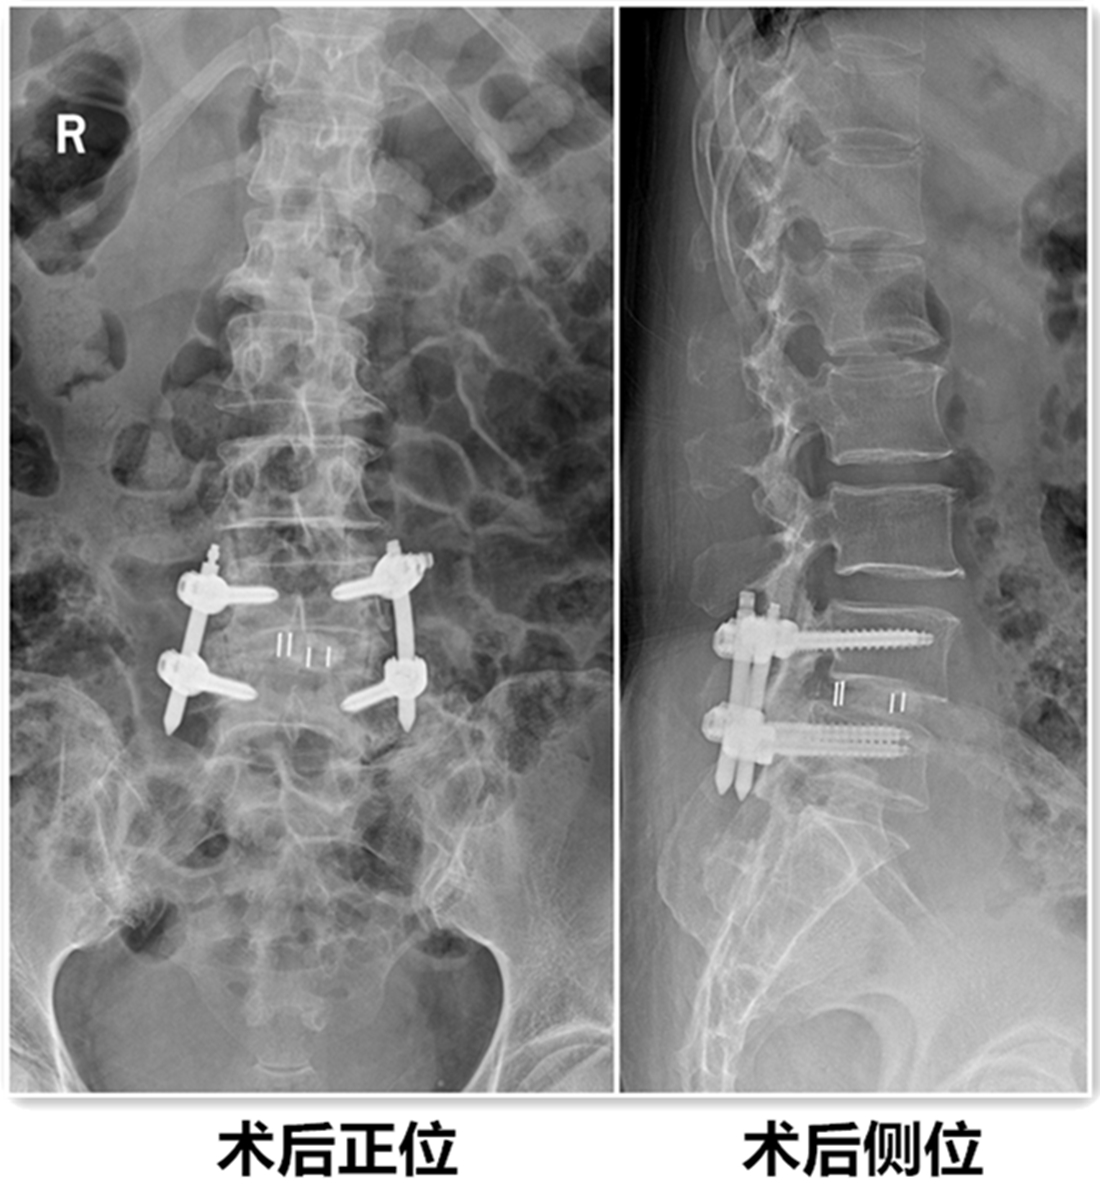

在使用国际领先水平的镜下处理工具及器械的同时,结合我院已有的天玑骨科手术机器人、神经电生理检测设备辅助下,我院安全、成功的完成了这台复杂手术。

患者术后第3天带支具下床活动,症状基本消失,并行X线检查。见滑脱复位,且椎间隙高度恢复。